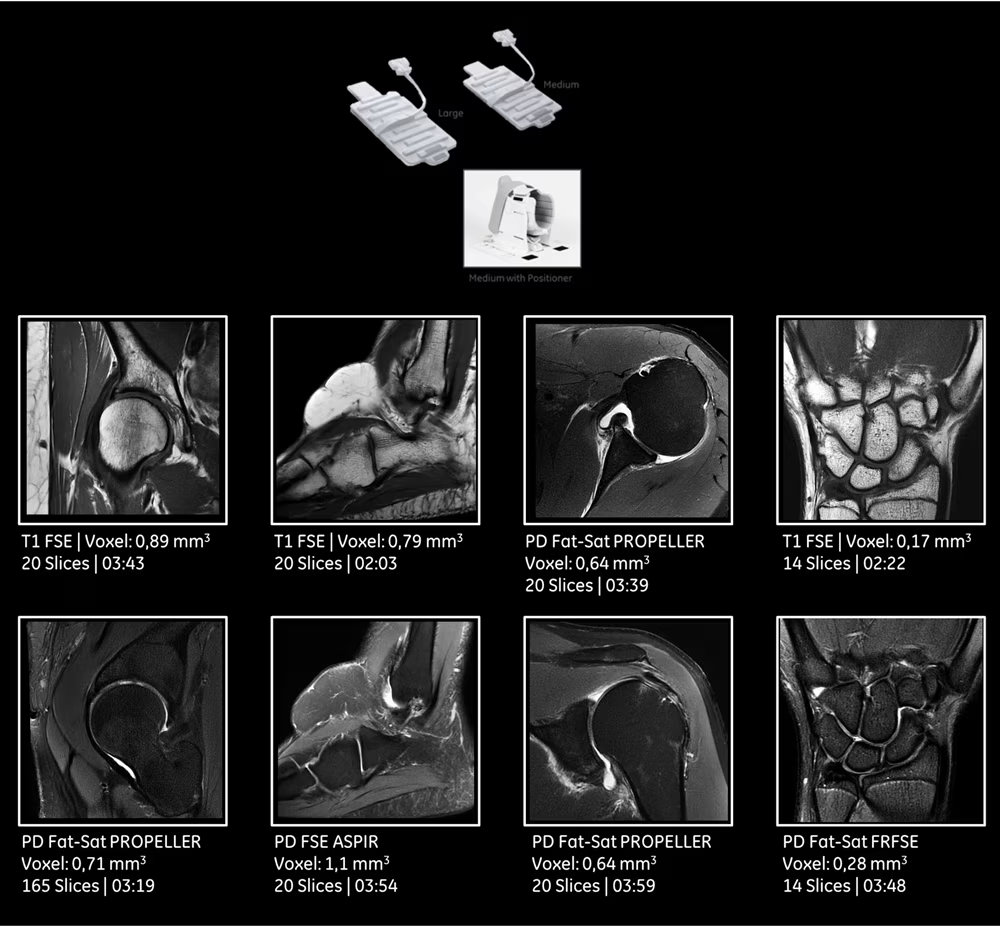

| Технология катушек | Совместимость с катушками AIR Technology и массивами для нейро-, body- и ортопедических протоколов |

| Специализированные протоколы для позвоночника и суставов | Высокодетализированные последовательности для оценки межпозвонковых дисков, суставных поверхностей, связочного аппарата и костного мозга. |